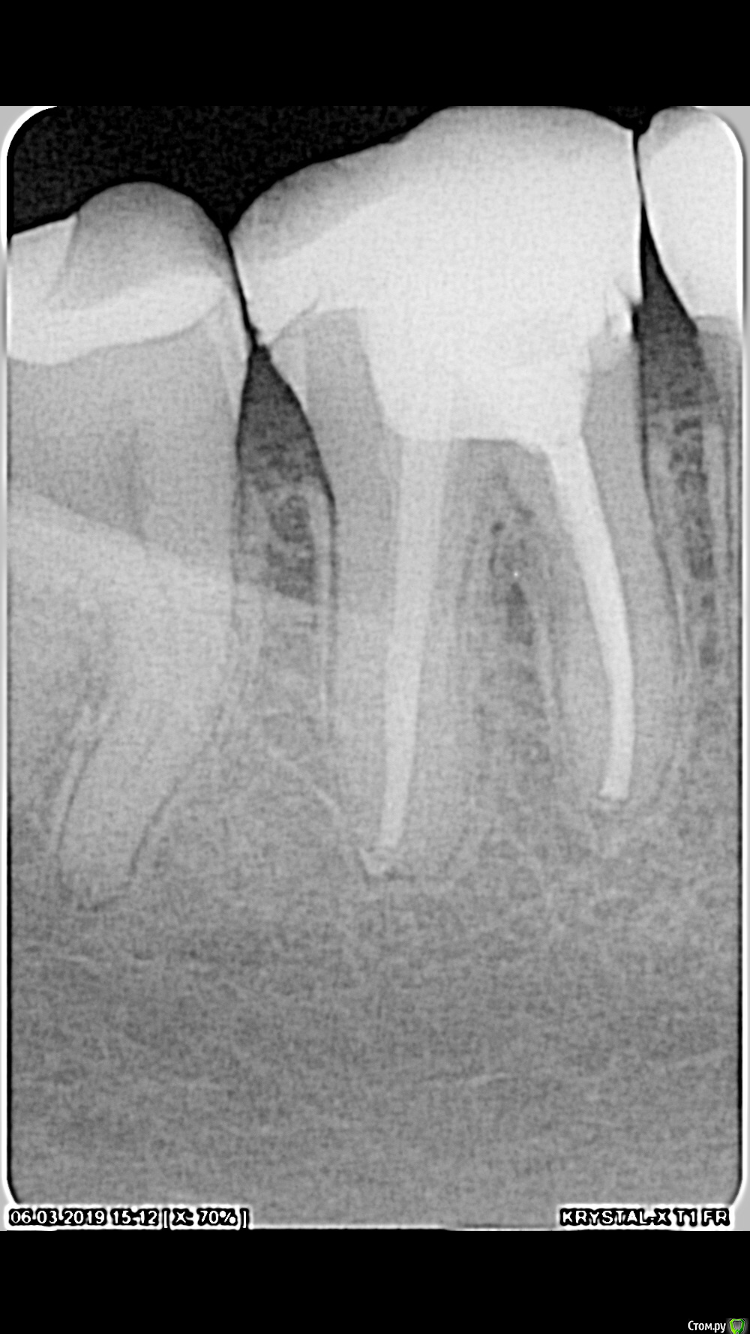

Elena Ren Опубликовано 24 мая, 2019 Поделиться Опубликовано 24 мая, 2019 Зуб был пролечен 6 месяцев назад. В настоящее время болит при надавливании и когда чищу зубы Ссылка на комментарий